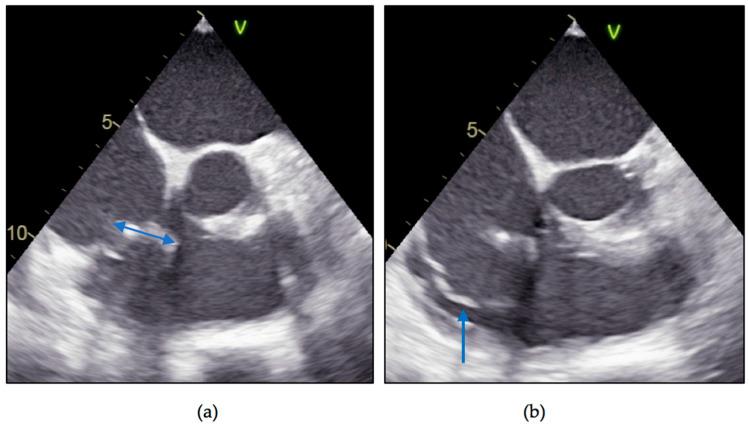

The number of infections related to cardiac implantable electronic devices (CIEDs) has increased as the number of devices implanted around the world has grown exponentially in recent years. CIED complications can sometimes be difficult to diagnose and manage, as in the case of lead-related infective endocarditis. We present the case of a 48-year-old male diagnosed with Staphylococcus aureus device-related infective endocarditis, 12 years after the implant of a single chamber pacemaker. A recent history of the patient includes two urinary catheterizations due to obstructive uropathy in the context of a prostatic adenoma, 2 months previously, both without antibiotic prophylaxis; no other possible entry sites were found and no history of other invasive procedures. After initiation of antibiotic therapy according to antibiotic susceptibility testing, we decided to remove the right ventricular passive fixation lead along with the vegetation and pacemaker generator; because of severe lead adhesions in the costoclavicular region, and especially in the right ventricle, we needed mechanical sheaths to remove the abundant fibrous tissue that encompassed the lead. After a difficult, but successful, lead extraction along with a large vegetation and 6 weeks' antibiotic therapy, the clinical and biological evolution was favorable, without reappearance of symptoms. While very late lead endocarditis is a rarity, late lead-related infective endocarditis (more than 12 months elapsed since implant) is not an exception; this is why we find that endocarditis prophylaxis should be reconsidered in certain patient categories, our patient being proof that procedures with neglectable endocarditis risk according to the guidelines can lead to bacterial endocarditis.

近年来,随着全球植入心脏植入式电子设备(CIED)的数量呈指数级增长,与CIED相关的感染数量也有所增加。CIED并发症有时难以诊断和处理,例如与导线相关的感染性心内膜炎。我们报告一例48岁男性患者,在植入单腔起搏器12年后被诊断为金黄色葡萄球菌设备相关感染性心内膜炎。患者近期病史包括2个月前因前列腺腺瘤导致梗阻性尿路病进行了两次导尿,均未进行抗生素预防;未发现其他可能的感染入口,也无其他侵入性操作史。根据抗生素敏感性试验开始抗生素治疗后,我们决定移除右心室被动固定导线、赘生物和起搏器发生器;由于锁骨下区域,尤其是右心室存在严重的导线粘连,我们需要使用机械鞘管来清除包裹导线的大量纤维组织。经过艰难但成功的导线拔除以及切除一大块赘生物,并进行了6周的抗生素治疗后,临床和生物学进展良好,症状未再出现。虽然极晚期导线心内膜炎较为罕见,但晚期导线相关感染性心内膜炎(植入后超过12个月)并不罕见;这就是为什么我们认为在某些患者类别中应重新考虑心内膜炎预防措施,我们的患者证明了根据指南心内膜炎风险可忽略不计的操作也可能导致细菌性心内膜炎。